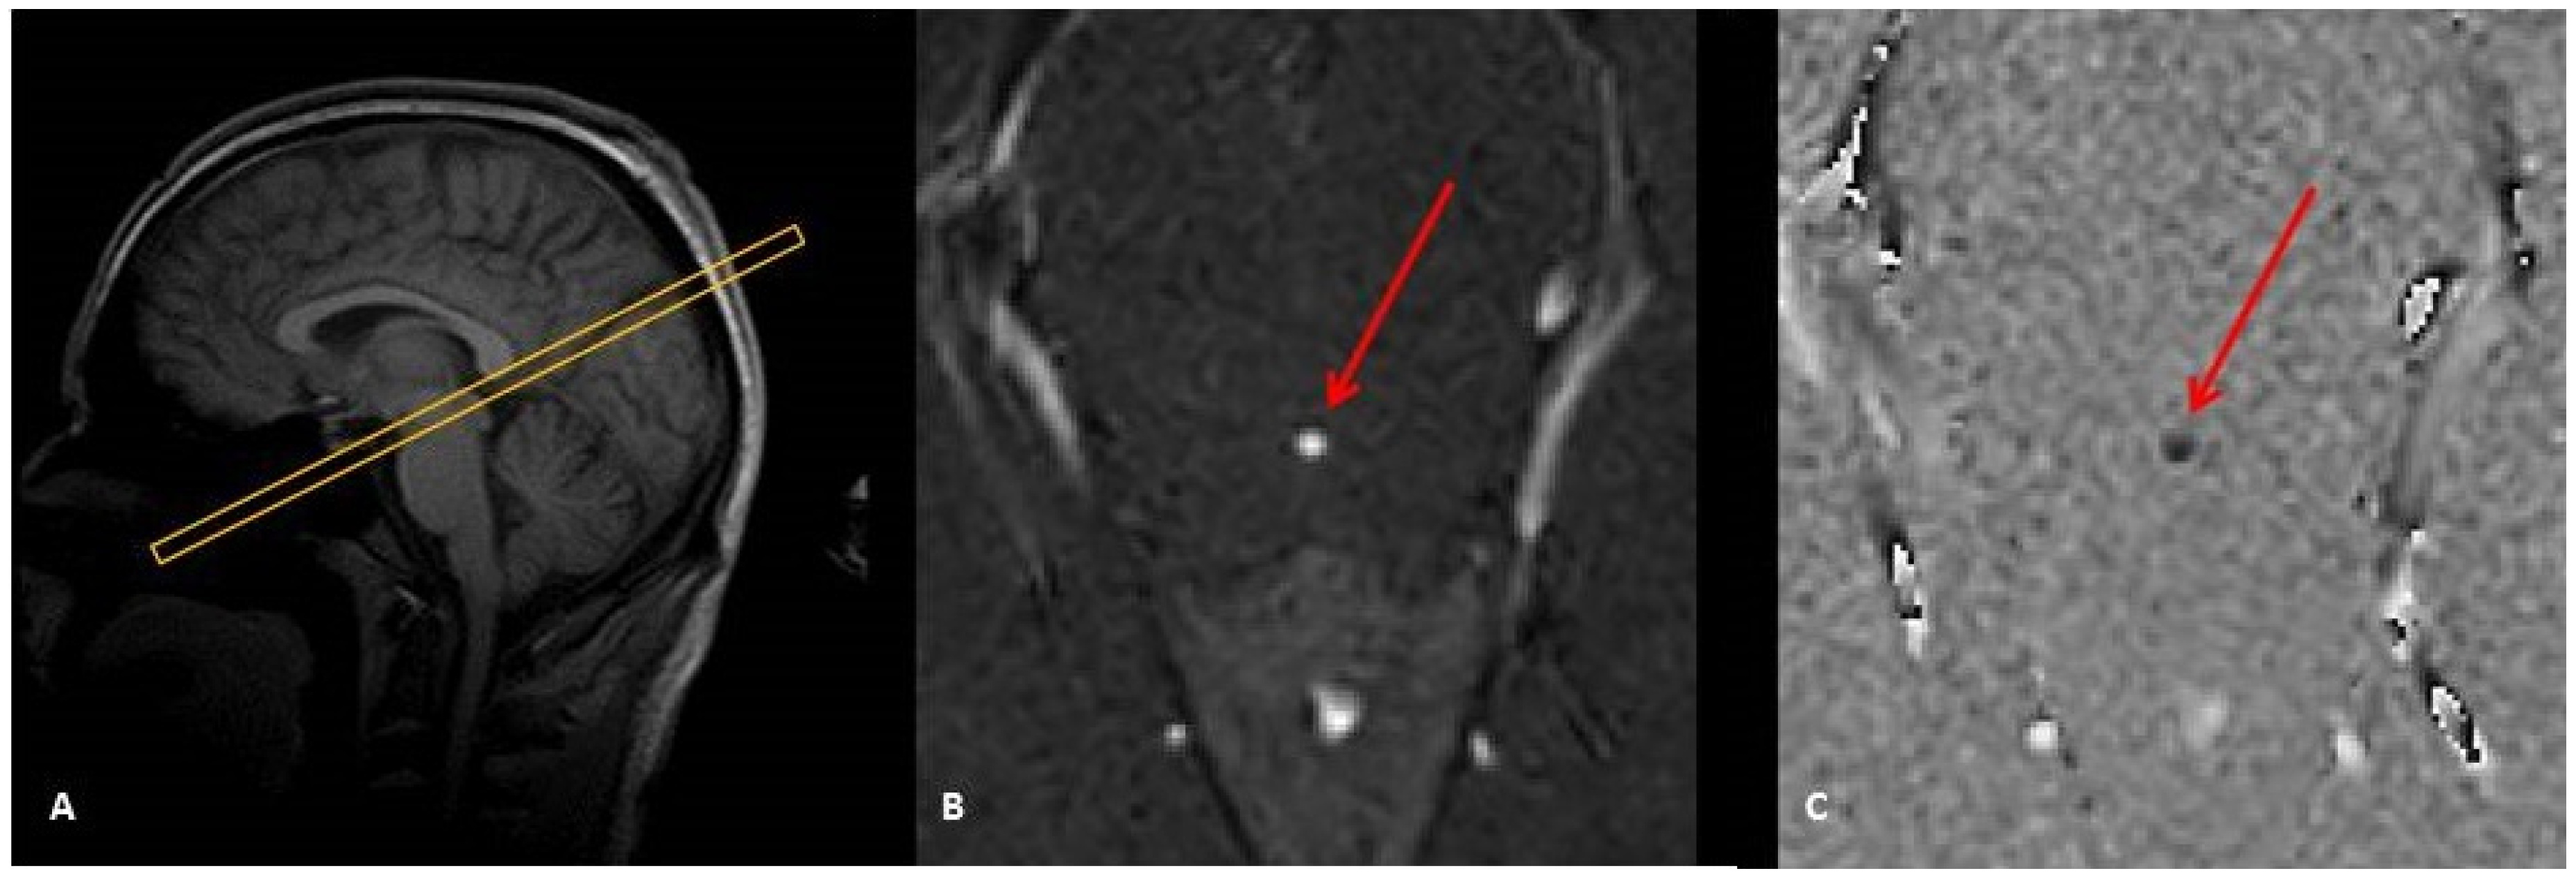

Figure 1. Sagittal image scout (A) to localize the aqueduct and to prescribe a perpendicular 2D Cine-phase MRI slice. This provides a magnitude image (B) suited to visualize and select the aqueduct (red arrow) and a phase-difference image to map the CSF flow (C). (B) and (C) represent one phase of the cardiac cycle.

The study was performed on a 3T Achieva dStream scanner (Philips Healthcare, Best, The Netherlands) equipped with a gradient strength G0 = 40 mT/m and a slew-rate SR = 200 T/m/s. The imaging parameters were: Cine-PC fast-field-echo (FFE) sequence, Cartesian filling with flow-compensation, Sense = 1.5, flip angle = 30°, and a 2 mm slice thickness. A comparative list of the imaging parameters between the two schemes is given in Table 1. An axial oblique slice was prescribed perpendicular to the aqueduct with a through plane Venc value of 100 mm/s to encode CSF flow velocity (Figure 1). For blood flow analysis, we chose the internal carotid artery (ICA) and Venc = 600 mm/s. The slice was prescribed perpendicular to the ICA at the level of the cervical spine C2–C3. Choosing either the jugular vein or the vertebral artery would answer the questions raised by this investigation. Since the main purpose of this study was to mimic the phase-offset errors on blood flow, there was no need to assess the total cerebral blood flow. The coverage-based comparison involved: (1) a full coverage of the whole head, referred as Full-FOV, and (2) a small FOV referred to as fold-over oversampling to remedy for aliasing. The experiments were performed on ten healthy volunteers with informed consent. The group included ten controls (25–55 years of age, five females) recruited in our university hospital. The inclusion criteria were no history of any neurologic disorder, or neurological development, or head trauma, and could hold still in the scanner. For the purpose of our study, a static phantom was filled with 3 L of water solidified with commercial 16 g of agar powder and 1 kg of sugar. Simultaneously after each acquisition from the volunteers, the phantom was scanned using the same imaging parameters and slice positions to measure the static phase-offset errors.